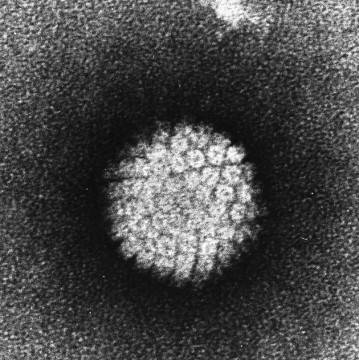

2002年11月12日

Koutsky和同事长达20年的探索发现了人类乳头瘤病毒(HPV)与宫颈癌之间的关系。这个双盲的随机对照试验发现,HPV疫苗接种完后的1.5年左右,HPV-16相关的宫颈癌几乎绝迹。仅仅4年后,FDA批准了四价HPV疫苗,用于预防宫颈、外阴和阴道肿瘤。尽管还有很多细节问题需要商榷,但HPV疫苗的出现也许意味着宫颈癌的末日。